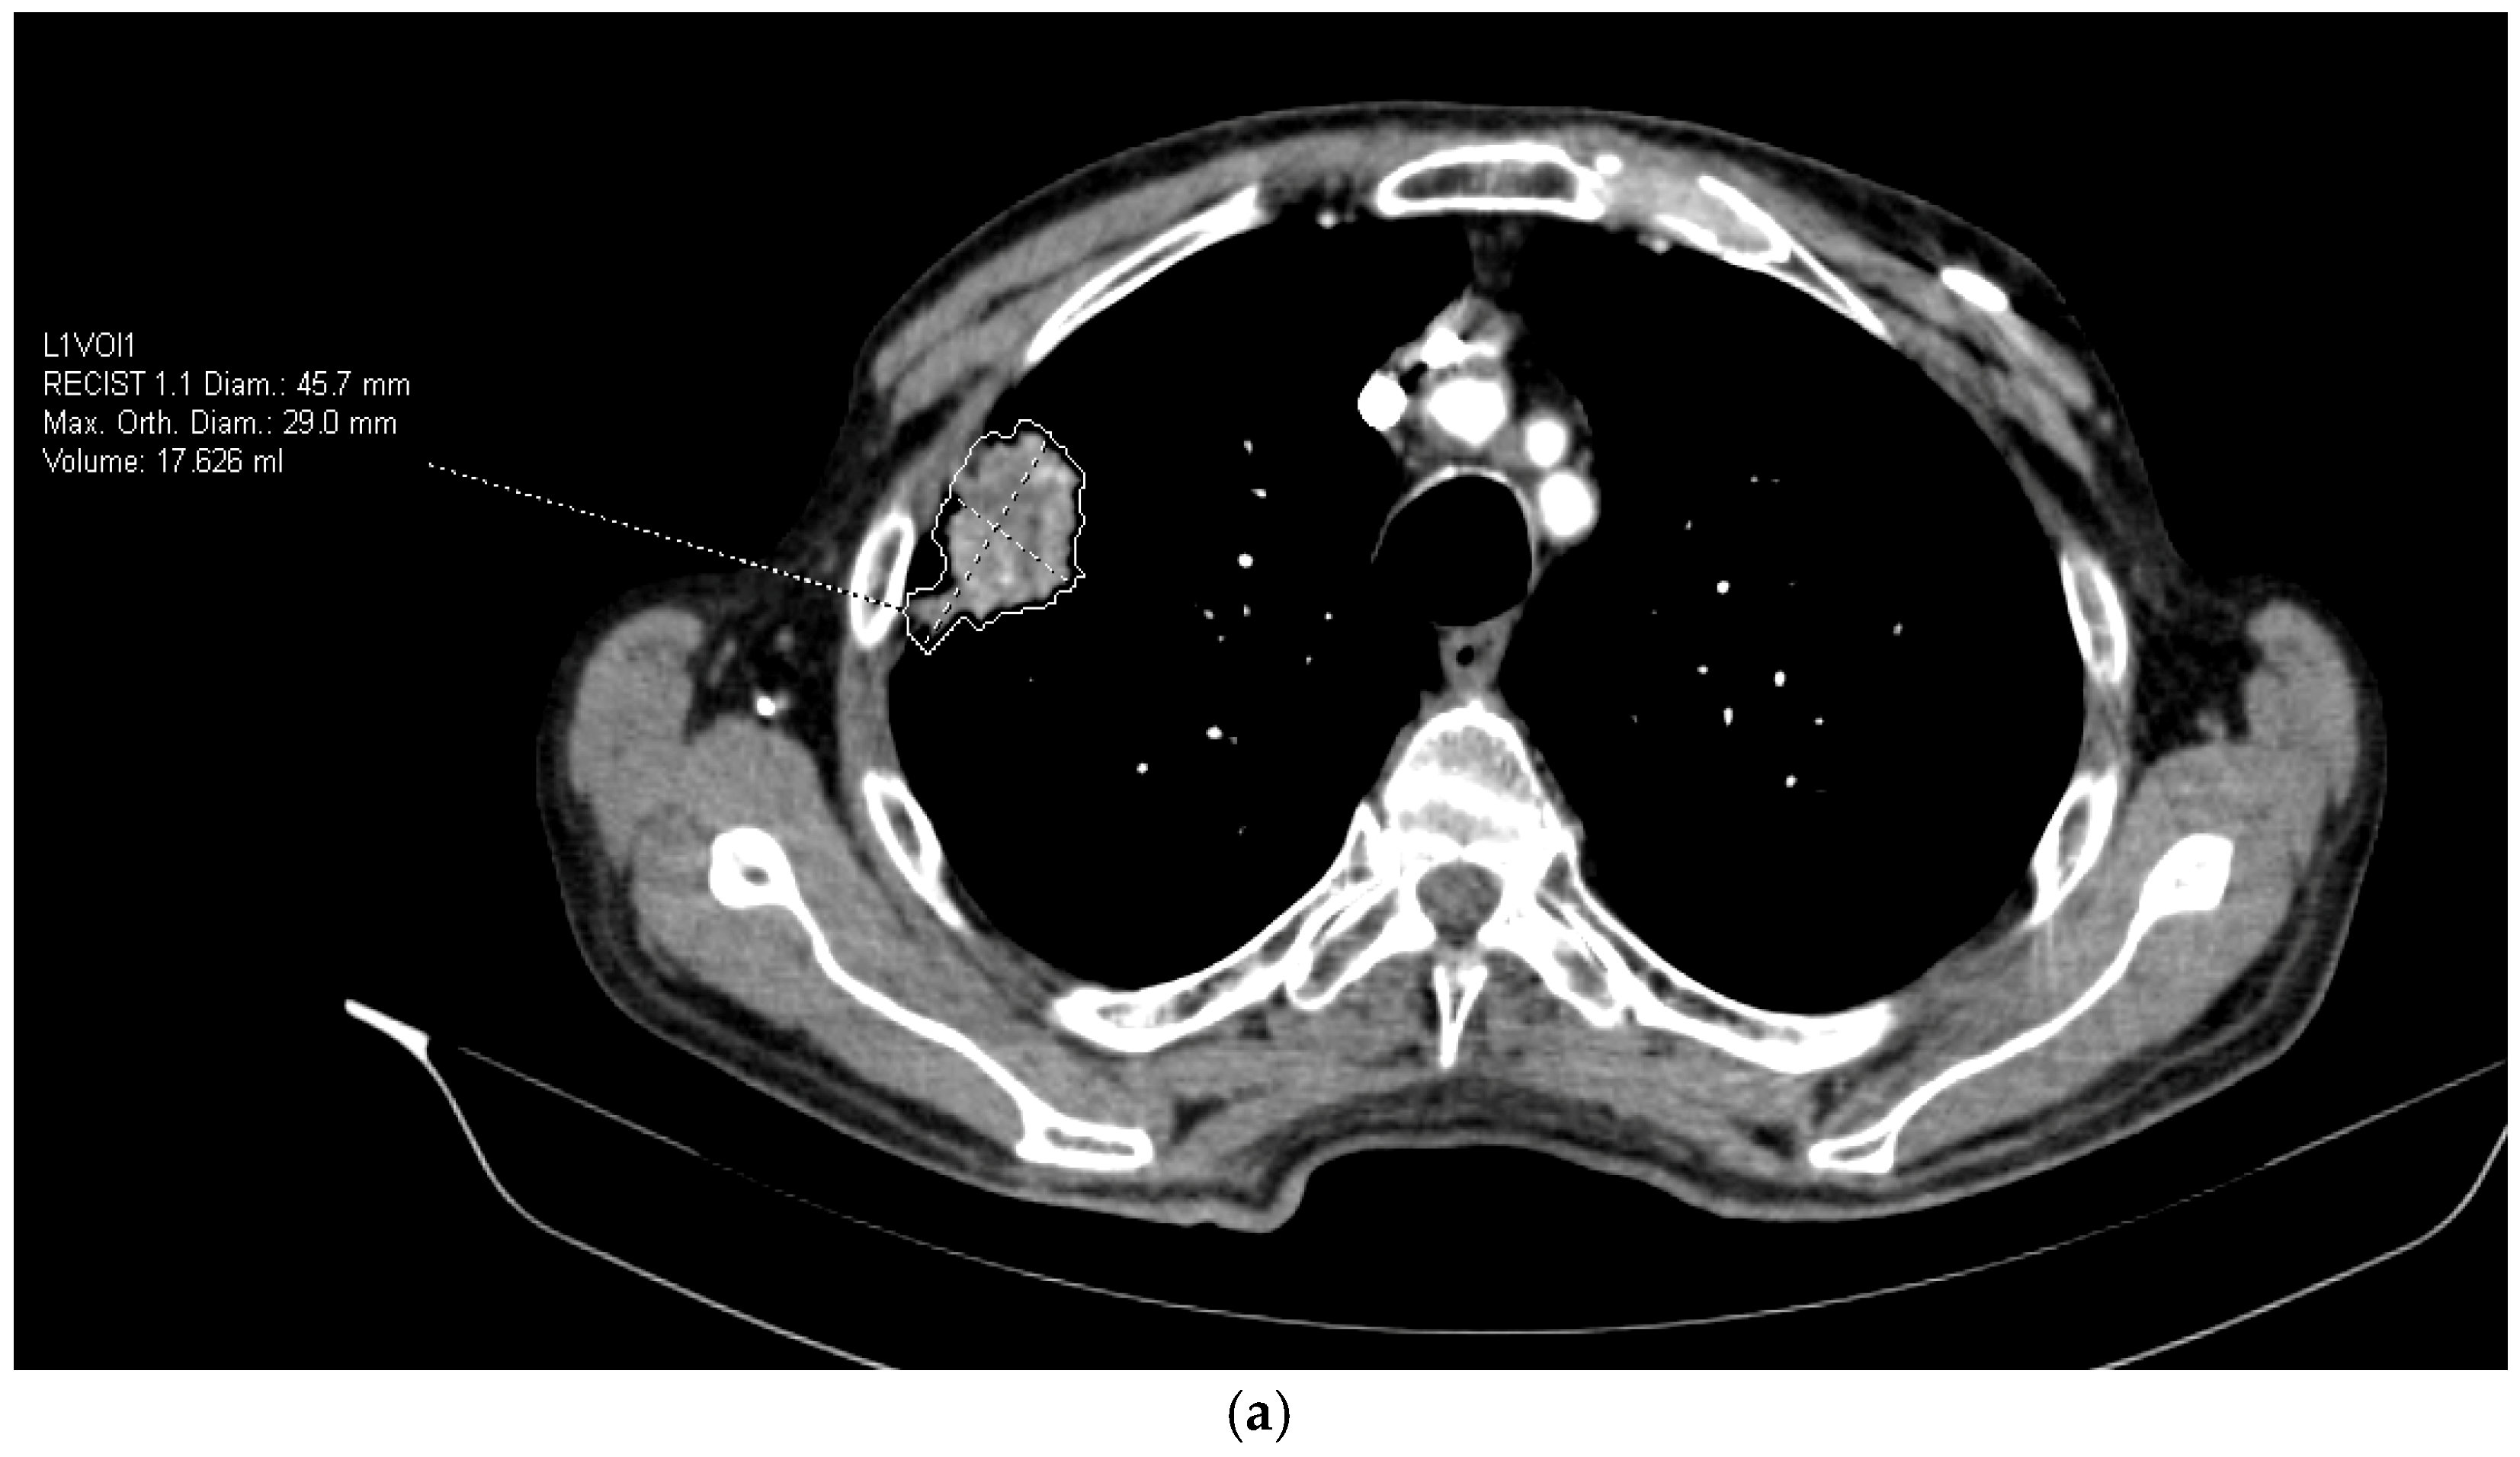

2.3. Radiomics Extraction from CT Images

- Lesion morphology: maximum diameter (mm), volume (mm3), shape irregularity;

- Texture features: mean attenuation, entropy, skewness, kurtosis, gray-level co-occurrence metrics;

| Diameter of the tumor * | 35.4 (15.8–102.6) | 35.6 (15.8–72.0) | 34.6 (17.8–102.6) | 0.588 |

| Volume of the tumor * | 11.468 (1.565–217.276) | 11.588 (1.565–158.455) | 11.935 (1.851–217.276) | 0.985 |